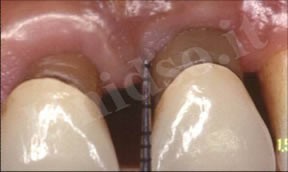

L’ Unità Operativa di Parodontologia e Igiene Orale si compone di 5 sezioni. L’attività’ clinico-assistenziale è svolta da diversi odontoiatri, supportata da igienisti dentali e assistenti alla poltrona, ed è articolata sulla base di appuntamenti programmati. Nell’Unità Operativa di Paradontologia e Igiene Orale del DSMOB si eseguono le seguenti prestazioni odontoiatriche: istruzioni d’igiene orale, ablazione tartaro, full radiografico, terapia dell’alitosi, levigatura radicolare, chirurgia parodontale riparativa, resettiva e rigenerativa e chirurgia plastica dei tessuti molli parodontali.